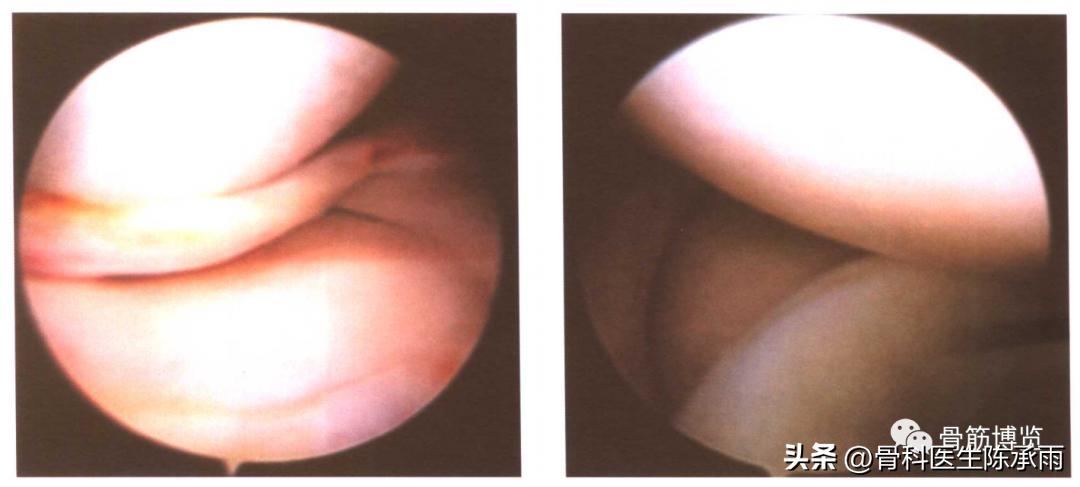

(一)纵裂

是指半月板的裂口与半月板纵轴相平行的撕裂。可以是垂直的,也可以是斜行的;可以是全层的,也可以是非全层的。常见于外伤直接的撞击或是随着关节囊的撕裂而形成。裂口为垂直方向的,与半月板边缘平行。其中又分为完全性的纵裂和不完全性的纵裂。完全性的(即全层的)纵裂,在裂口较大时,其内侧游离缘部分可以脱位于髁间窝,即形成典型的提篮状或者桶柄状撕裂。这种损伤容易导致关节绞锁,使关节屈伸受限。当撕裂时间较短,内侧的游离部分较完整,尚能较好地复位时,可以施行半月板缝合术,特别是接近滑膜缘的纵裂,缝合的效果较好,成功率较高。如果是不完全性的(即非全层的)纵裂则往往合并有层裂或斜裂,探查时应予注意。